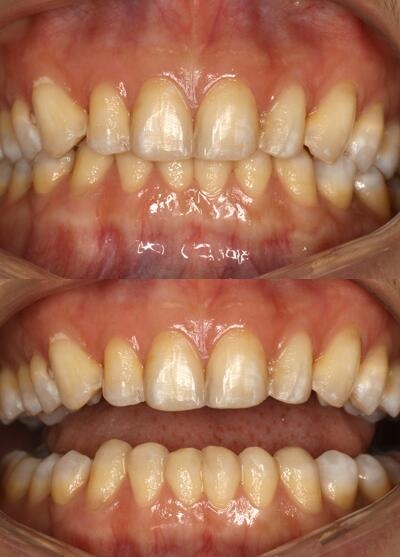

口腔专科检查:全口牙色呈黄褐色斑点状,13-23颊向倾伴生长,12-22舌向内倾,33-43舌向内倾伴磨耗,咬合为深覆颌,牙周良好,微笑时露龈。

氟斑牙|瓷贴面修复——术前照片

术前正面照